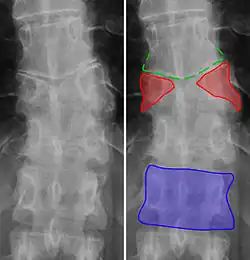

-

Butterfly vertebra (red). Normal vertebra for comparison (blue). -

Volume rendering of a CT scan of the lumbar vertebral column, showing butterfly vertebrae at several levels, most typically in L1.